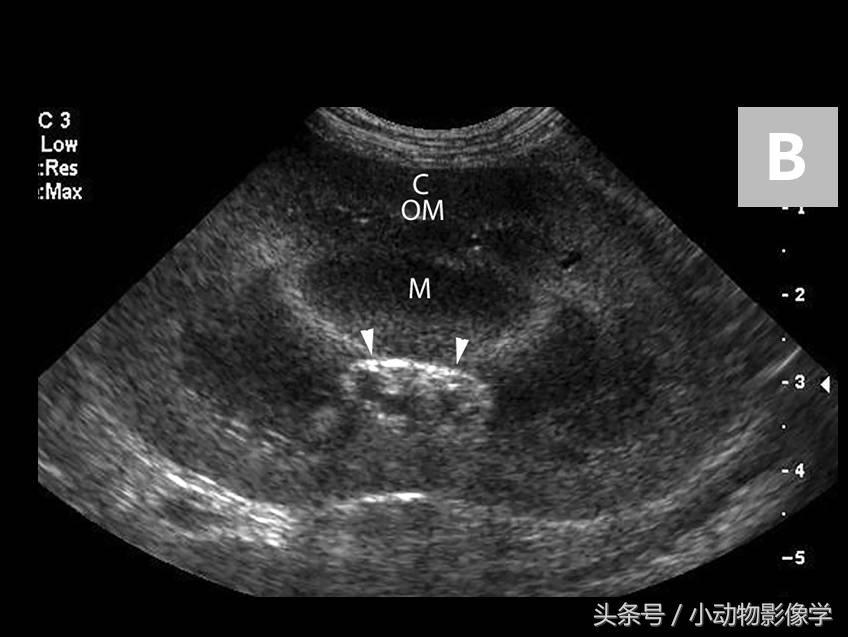

图1B、犬正常左肾的背面观超声图像。注意外层高回声肾皮质(C)和外层肾髓质(OM)(这两者无法区分),以及内层均匀的低回声肾髓质(M)。肾盂在肾脏的深部或中部呈直角状括弧(箭头)。